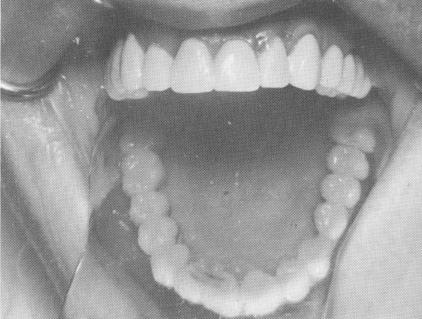

Fig. 10-174. The right posterior quadrant is cemented into position utilizing the lateral incisor thimble and molar tooth preparation as the abutments.

Fig. 10-175. The left posterior quadrant cemented into position.

2 Maxillary right posterior quadrant cemented into position